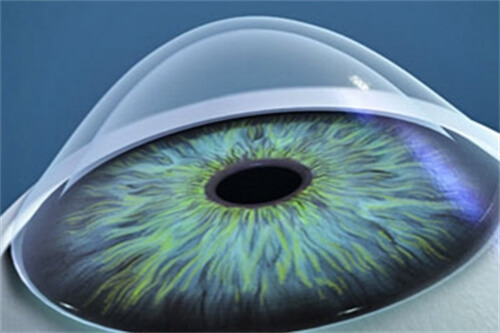

术前:采用Pentacam三维眼前节分析仪进行角膜生物力学评估

术中:使用龙晶PR人工晶体(国产初款睫状沟固定型晶体)增强角膜稳定性

术后:提供RGP验配服务,矫正不规则散光

采用Corvis ST角膜生物力学分析仪,比较准测量角膜抗变形能力。